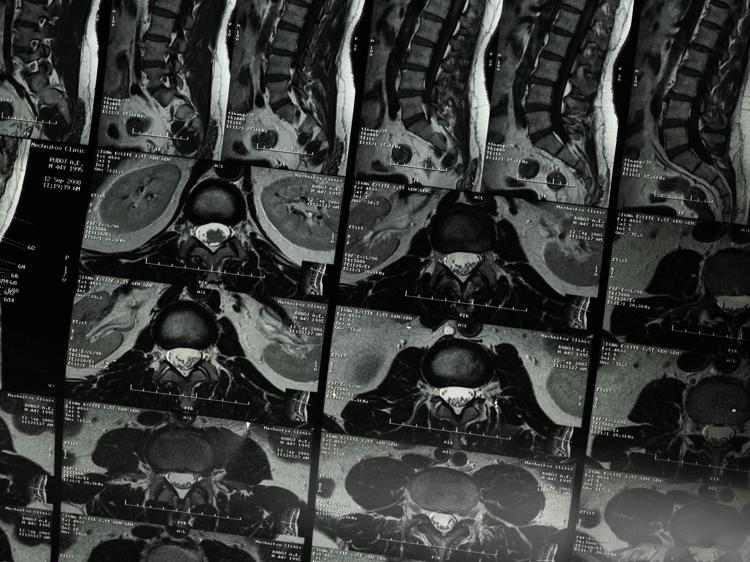

出现左腿发麻时,千万别自己瞎猜病因或乱吃药,得及时去正规医院的骨科或神经内科看医生,通过腰椎CT、磁共振成像(MRI)这些检查,明确是不是腰椎骨质增生压迫神经导致的。如果确诊了,可在医生指导下做这些干预: 一是药物治疗,遵医嘱用抗炎药(比如布洛芬,能缓解神经受压引发的炎症)、活血化瘀药(比如三七片,改善局部血液循环)、营养神经药(比如甲钴胺,帮助神经修复)。这些药必须严格按医嘱用,不能自己加量、减量或停药,也不能替代神经减压治疗;孕妇、哺乳期女性、肝肾功能不好的人用前一定要问医生,确保安全。 二是局部理疗,热敷能促进血液循环、缓解肌肉紧张,不过温度要控制在40-50摄氏度,每次15-20分钟,别烫到皮肤;按摩得让专业康复师或医生做,别乱按以免加重神经损伤。此外牵引、针灸也可能有用,但腰椎骨折、严重骨质疏松的人做理疗前得问医生,排除禁忌。